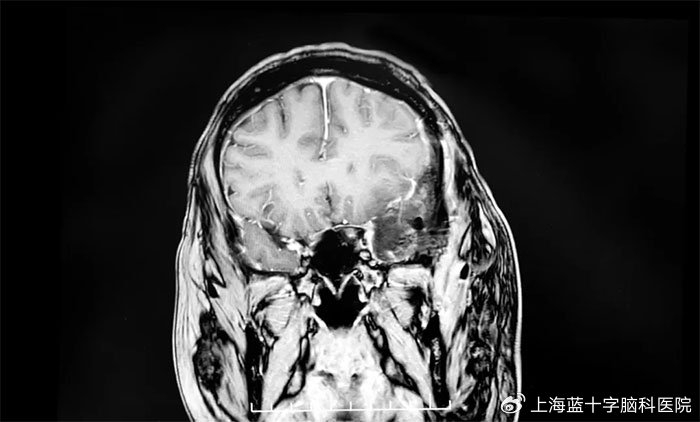

3、如果肿瘤位于特定部位,早期也可能会出现特征性的症状脑部良性肿瘤最常见的是脑膜瘤和垂体瘤,脑膜瘤位于额顶叶部位时,导致患者出现肢体麻木偏瘫位于前颅底嗅沟部位时,导致患者嗅觉下降甚至丧失位于内听道附近时会出现耳鸣听力下降垂体瘤位于蝶鞍区时会导致患者视力下降以及内分泌紊乱的症状;但初期症状通常不会特别严重4 认知功能下降 脑袋长瘤初期,患者可能会出现记忆力下降或性格改变 这些症状都是一个慢性的过程,往往不容易被察觉以上症状在初期可能并不明显,且容易被忽视因此,如有长期存在的上述症状,建议及时就医检查,以便早期发现和治疗脑部肿瘤;9 其他症状肿瘤还可能引起面部麻木嗅觉丧失吞咽困难或内分泌紊乱如肢端肥大症需强调的是,上述症状并非脑部肿瘤特有,也可能由其他疾病导致若症状持续或加重,应尽快就医,通过磁共振成像MRI或计算机断层扫描CT等检查明确病因早期诊断和治疗可显著提高治愈率,高风险人群如家族史者长期接触致癌物质者更需定期筛查。

5、1 头痛头痛是脑部肿瘤最常见的症状之一,通常逐渐加重,可能发生在头部一侧或双侧疼痛可能伴随恶心呕吐或视觉障碍如模糊闪光,尤其在晨起或体位改变时加重这与肿瘤压迫脑组织或引发颅内压升高有关2 癫痫发作肿瘤可能刺激脑神经元异常放电,导致突然反复的抽搐发作形式包括全身性抽搐或;脑部恶性肿瘤在早期的主要症状包括头晕头痛这是最常见的早期症状,但这种头晕头痛通常不显著,且经过休息后能有所缓解,因此容易被忽视肢体抽搐患者可能会出现癫痫大发作或局灶性癫痫发作的症状,这通常是由于肿瘤刺激大脑的神经元,导致神经元异常高频放电所引起的神经功能障碍早期恶性肿瘤可能;1头痛头痛是脑部肿瘤最常见的症状之一,通常呈逐渐加重趋势疼痛部位可能涉及头部任意区域,性质可为搏动性或持续性,夜间或晨起时可能加重,与颅内压升高或肿瘤直接刺激脑膜有关2呕吐呕吐常与头痛伴随出现,多因颅内压升高刺激呕吐中枢所致,尤其在晨起或进食后更明显,可能呈喷射性3视力问题肿瘤;脑部肿瘤早期症状多样,具体表现如下1 头痛颅内压升高或肿瘤直接刺激脑膜血管及神经时,早期表现为间歇性胀痛,随病情进展逐渐加重,发展为持续性头痛,常在清晨或夜间加重,咳嗽弯腰时可能加剧2 呕吐多与剧烈头痛同时出现,呕吐后头痛可暂时缓解此症状与颅内压增高导致延髓呕吐中枢受刺激有关;脑部肿瘤的前期症状多种多样,一定要根据实际情况进行判断,一般情况下而言,往往会出现头痛头晕恶心呕吐等相应的症状,基本上是所有的脑部肿瘤都会出现的表现如果脑部肿瘤发生在额叶,则可能会造成认知功能的障碍或者认知功能的下降,以及出现了肢体的偏瘫,如果肿瘤生长在枕叶,则可能会造成视力模糊。